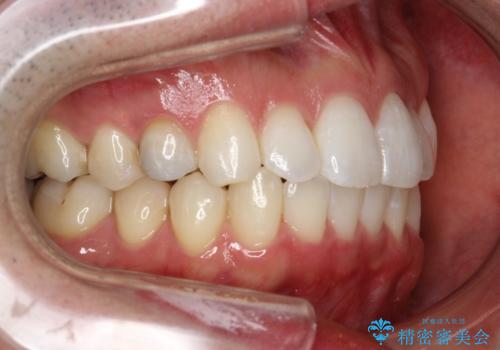

フルリンガルは違和感も強く操作も煩雑になるため、あまりおすすめはしていませんが、お仕事の都合などでどうしても装置を付けられない&マウスピースを管理することができない、場合はやむなく選択することもあります。

フルリンガル矯正 非抜歯でガタつきを整える

- フルリンガルワイヤーによる非抜歯治療を計画しました。